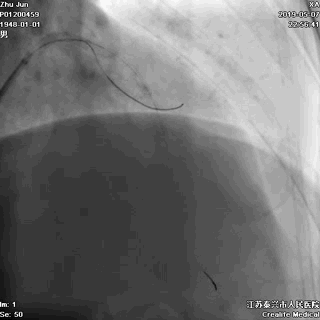

三、球囊扩张病变

---打通生命通道

前降支至左主干行PTCA